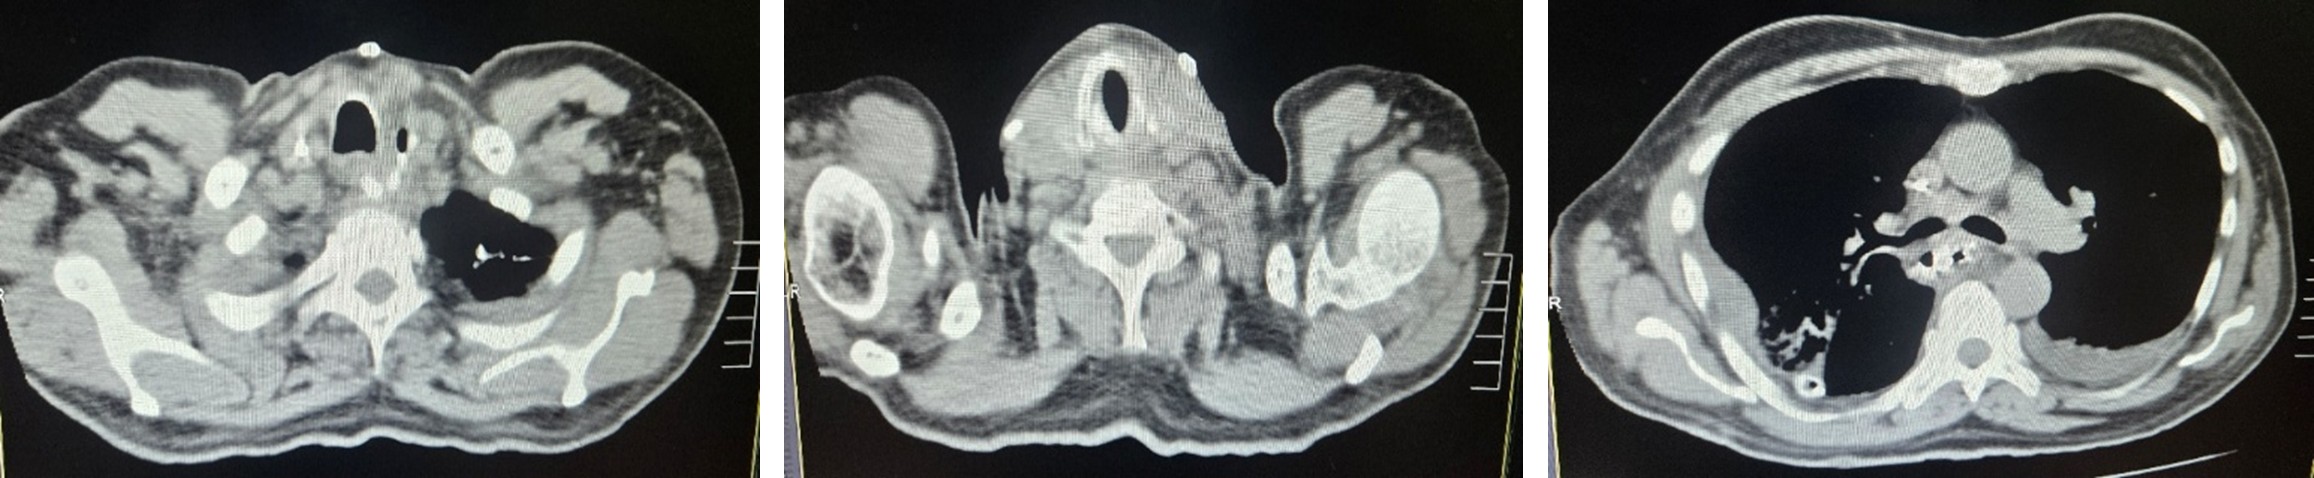

CT Chest & Abdomen

- Circumferential wall thickening of the lower esophagus.

- Mild regional lymphadenopathy.

- No distant metastasis.

Post operative CT abdomen

A contrast enhanced CT scan of the chest and abdomen was performed to rule out an anastomotic leak. The scan showed no evidence of leak but revealed bilateral lung infiltrates with collapse of the right basal lobe. Due to respiratory compromise, the patient was shifted back to the ICU for advanced respiratory care. Broad-spectrum antimicrobial therapy including Colistin and antifungal agents was initiated as per pulmonologist recommendations. Intensive pulmonary rehabilitation was continued.